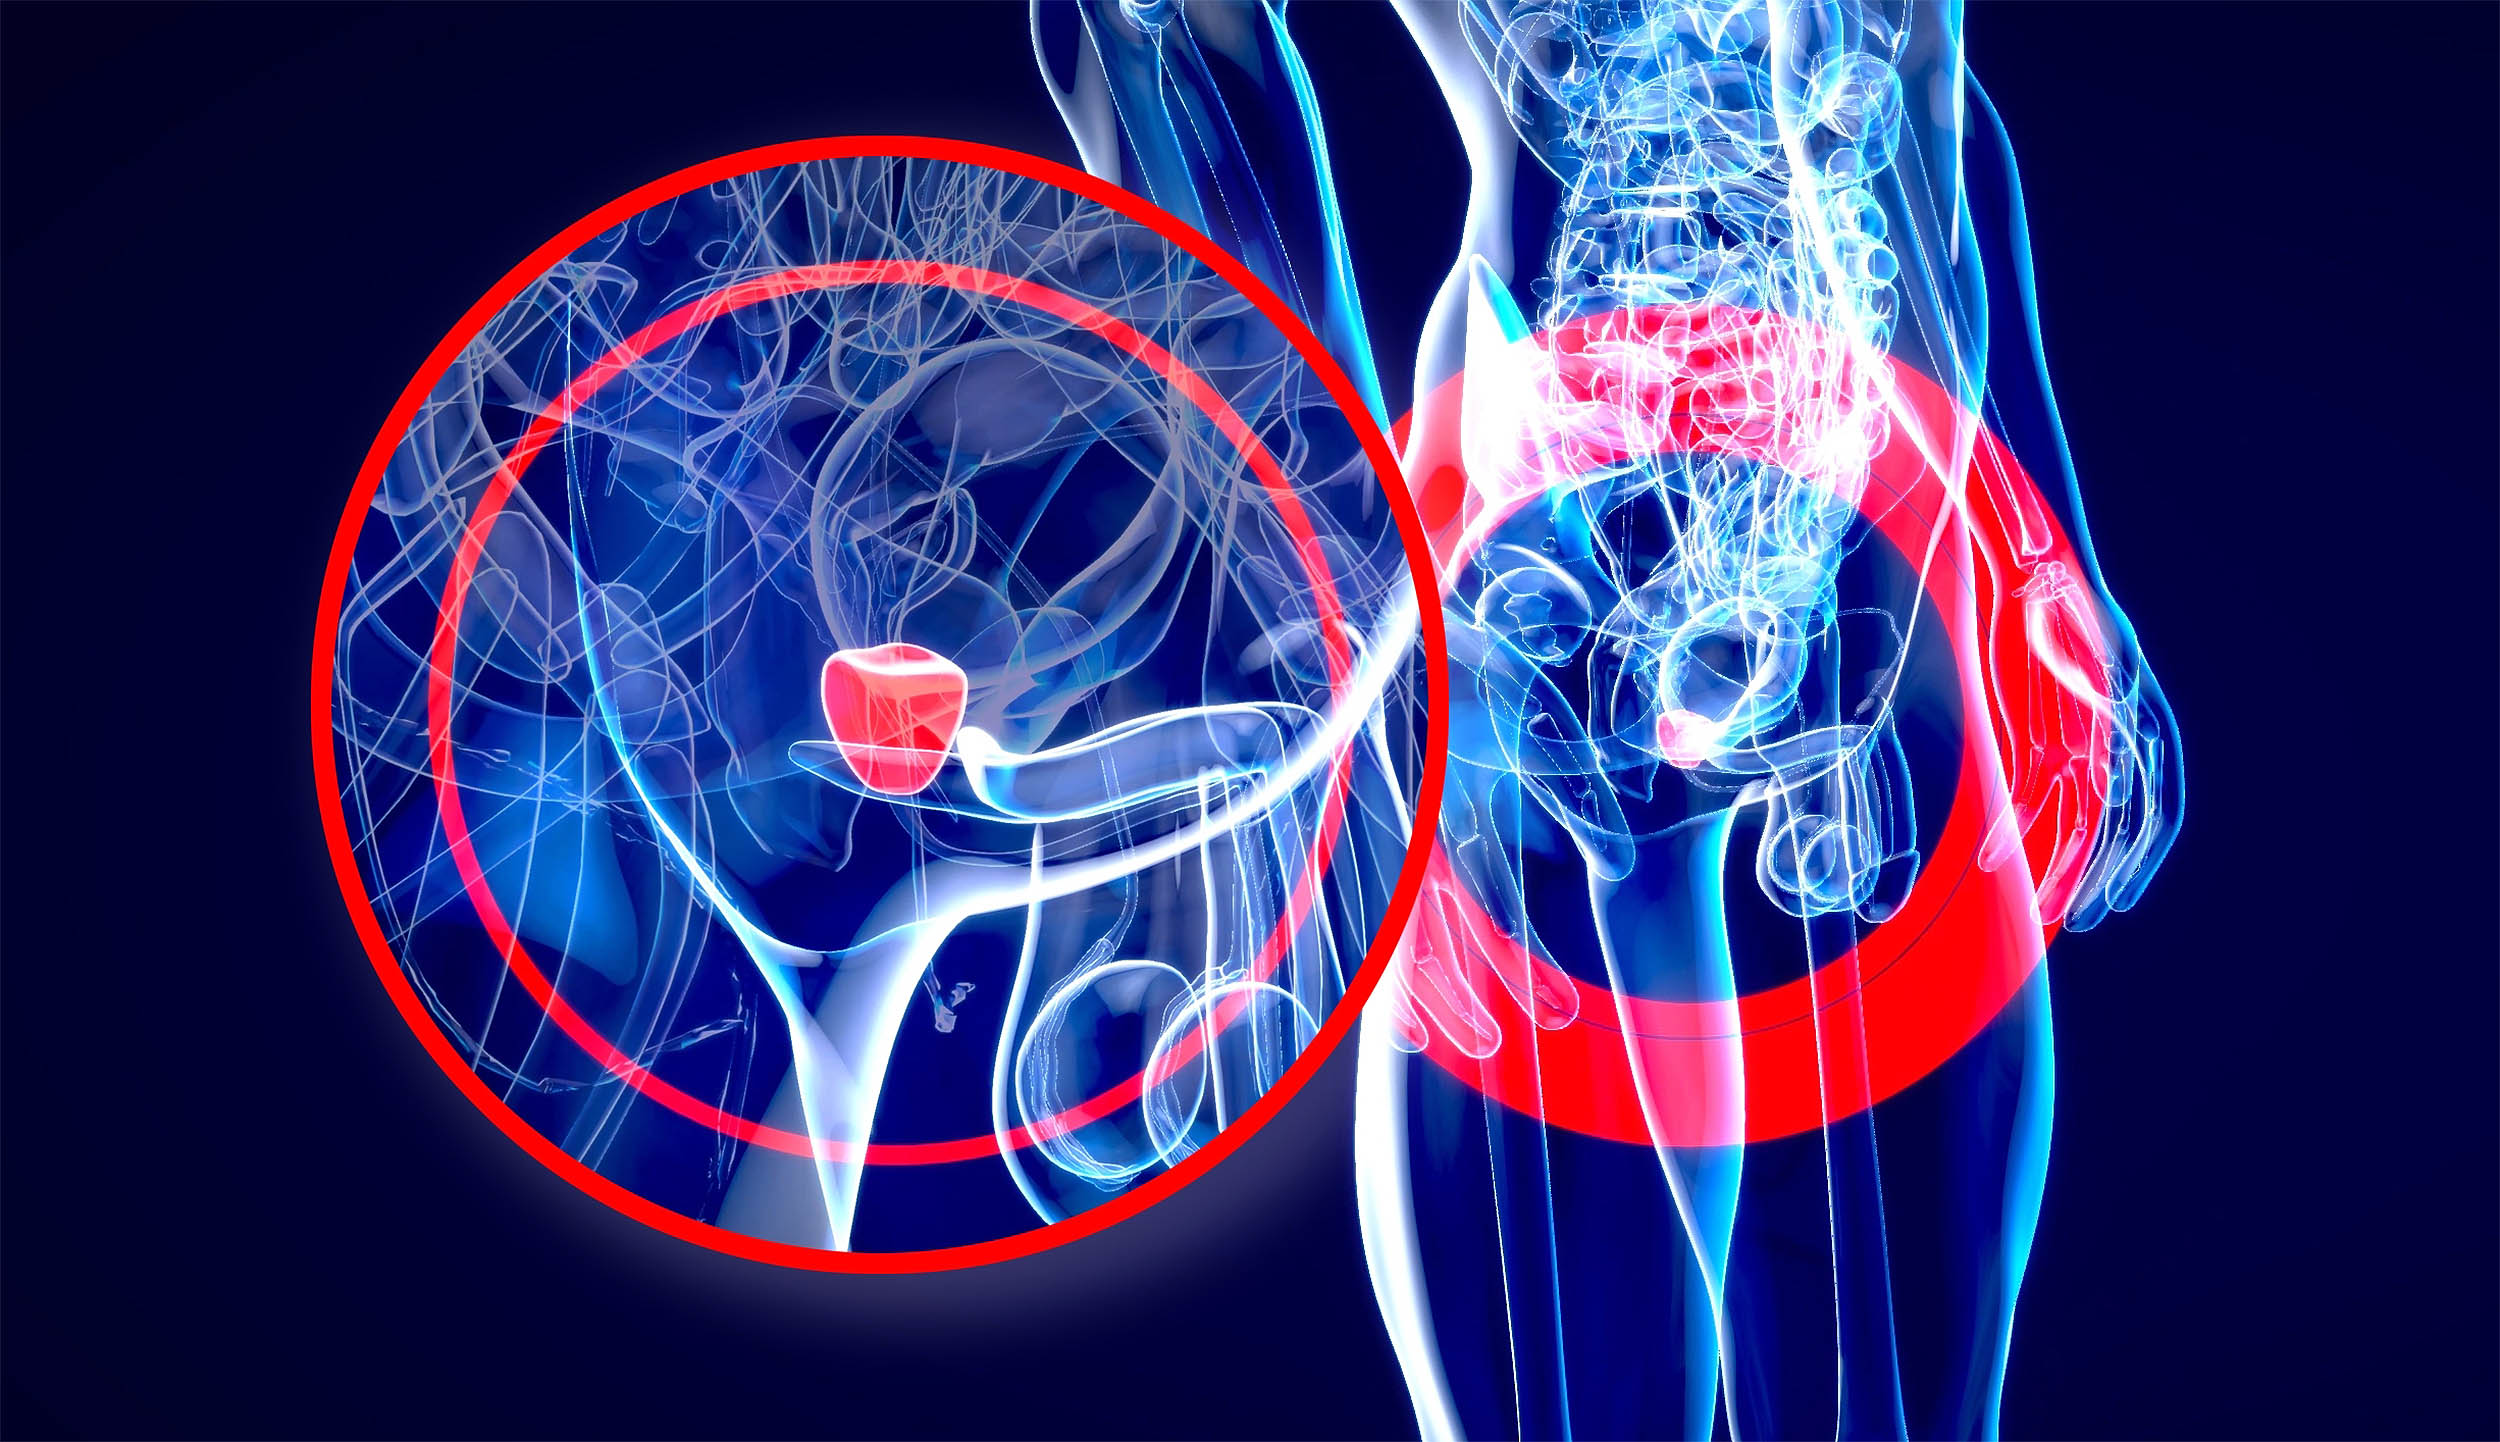

An experimental drug pairing slowed the spread of advanced prostate cancer on scans in men whose tumors carry BRCA mutations.

In a large, international trial across 32 countries, adding niraparib to abiraterone and prednisone cut the risk of…